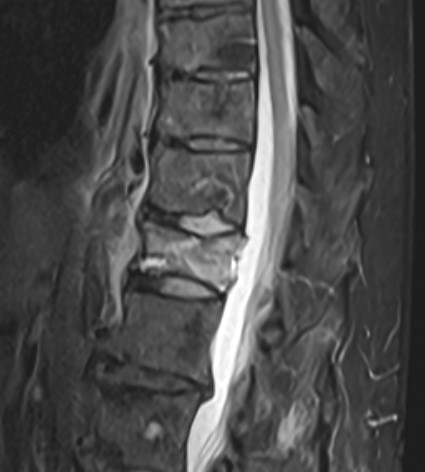

MRI STIR Sequenz der Wirbelsäule

Abbildung einer spinalen STIR Sequenz im MRI eines Patienten mit einem intraspinalem Abszess.